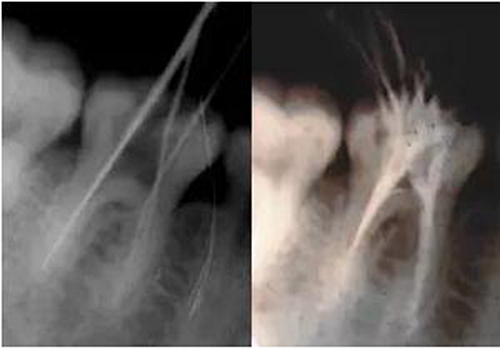

最后來(lái)玩一個(gè)根管治療質(zhì)量的評(píng)估——下圖是武大彭彬教授的一個(gè)病例,仔細(xì)觀察可以挑出一點(diǎn)問(wèn)題,但問(wèn)題事出有因!看看你的“眼力”如何——問(wèn)題在那里?教授的專(zhuān)業(yè)水平是不用懷疑的,那么事出的原因可能是什么?

問(wèn)題答案:這個(gè)病例的問(wèn)題主要反應(yīng)在開(kāi)髓的洞形修整,注意觀察該牙X-RAY的左側(cè)洞壁,如果常規(guī)情況制備成這樣是由于裂鉆破壞了洞壁和洞底所形成的臺(tái)階。如果評(píng)估根管治療的質(zhì)量那是要扣分的!但這個(gè)病例仔細(xì)觀察洞壁形態(tài)就可以看出:該病例屬于再治療的病例,因此還是屬于一個(gè)理想的病例。